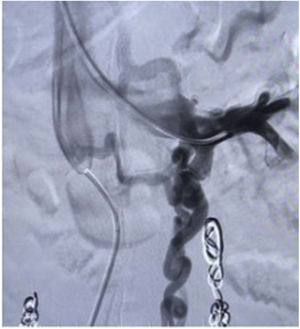

Surgical techniqueThe principles applied were urgent LRV pressure control, treatment of the hematuria, venous drainage derivation and congestive pelvic syndrome origin resolution. All the patients remain 24h postoperative in hospital observation. The repair was performed via endovascular access, after local anesthesia and sedation. The right common femoral and the left internal jugular vein was punctured with ultrasound guide and a 6F introducers sheath were inserted. The LRV was catheterized with a Cobra 2 5F diagnostic catheter and phlebography was performed. This confirmed critical stenosis of the LRV and the pelvic varicose veins on the left, with a dilated left gonadal vein (Fig. 1). The stenosis pressure gradient was measured in all patients. Through the internal jugular access, balloon LRV angioplasty was performed (Fig. 2) and then deployment of a e-Luminex self-expanding nitinol bare metal arterial stent (10–12mm×40mm) (Figs. 3 and 4) was performed resolving the NCS (Fig. 5). Additionally, identified pelvic varicose veins were embolized using Concerto coils (20mm×50mm) through the basilic vein using a multi-purpose catheter. No dietary restrictions were imposed, and oral food intake was initiated in the first 3 postoperative hours. No need for a postoperative ICU. Postoperative anticoagulation for 6 months using rivaroxaban and then switching to salicylic acid for another 6 months was prescribed to all patients. The postoperative patients follow-up was performed using Doppler ultrasound in the 6 months and physical examination in all face-to-face clinical outpatient consults.

During the period from January 2019 to April 2022, 553 patients were treated for congestive pelvic syndrome. Only 11 patients have clinical (hematuria, varicose pelvic veins, and left flank pain), imaging diagnostic criteria (abdominal veins Doppler ultrasound or abdominal CT with a SMA – abdominal aorta angle less than 39°) and an average of LRV–IVC pressure measurement comparison difference of 6mmHg for NCS. The 100% were female patients. All the patients were under 65 years old and underwent endovascular approach with LRV balloon and arterial stent angioplasty. The 100% of patients had collateral venous flow restored in the final control phlebo-cavography. The average age was 46.5 years old. Ten of the patients had an anterior type of NCS and only 1 had a posterior type of NCS (Fig. 6). None of the patients had NCS due to secondary causes such as pancreatic head tumors.

The mean operative time was 54min. The average bleeding time was 5cc. Length of hospital stay was 1 day (minimal bleeding and length of hospital stay). None of the patients required UCI. No complications or interventions were observed. The mortality was 0%. All patients were taken to pelvic varicose vein endovascular embolization. The 11 patients presented an average symptom resolution of 100%. No stent or LRV thrombosis was reported. No stent migration or other related complications were presented. No need of open or endovascular reintervention was presented in this case series. We suggest follow-up with iliocaval echo-Doppler every 6 months to assess the integrity of the venous system.